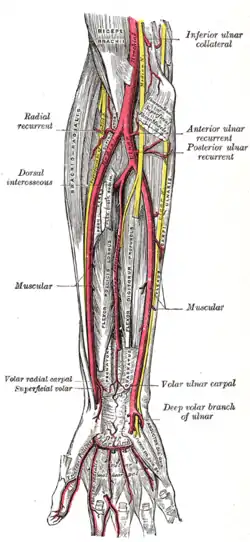

Transverse section across the wrist and digits. Ulnar and radial arteries. Deep view.

Ulnar and radial arteries. Deep view. The right brachial plexus (infraclavicular portion) in the axillary fossa; viewed from below and in front.